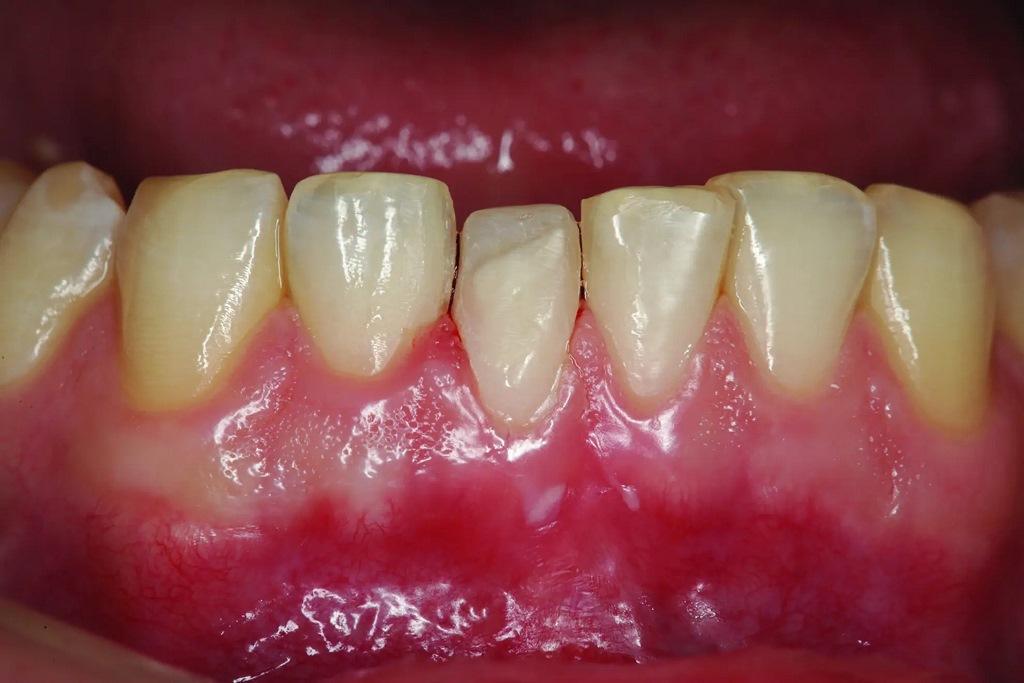

А как насчет выравнивания зубов-антагонистов? На режущих краях зубов 31 и 41 (фото 2) наблюдался чрезмерный износ. Со стороны резцов был виден значительный износ всех краев нижней челюсти из-за окклюзионного заболевания, которое часто наблюдается, но не лечится (фото 3). Также зуб 41 располагался на лицевой стороне таким образом, что при выступающей экскурсии он преждевременно соприкасался с небной поверхностью зуба 11, создавая дополнительную нагрузку как на небную поверхность, так и на резцовый край зуба 11, прежде чем соединиться с остальной частью переднего сегмента верхней челюсти. Это демонстрирует, что решение этих проблем реставрационными методами включает в себя нечто большее, чем просто исправление сколов композитной реставрации.

Фото 2: Зубы выступают вперед, что свидетельствует о чрезмерном износе зуба (41), расположенного напротив зуба 11, что указывает на гиперфункцию и повышенную функциональную нагрузку на восстановленную область.